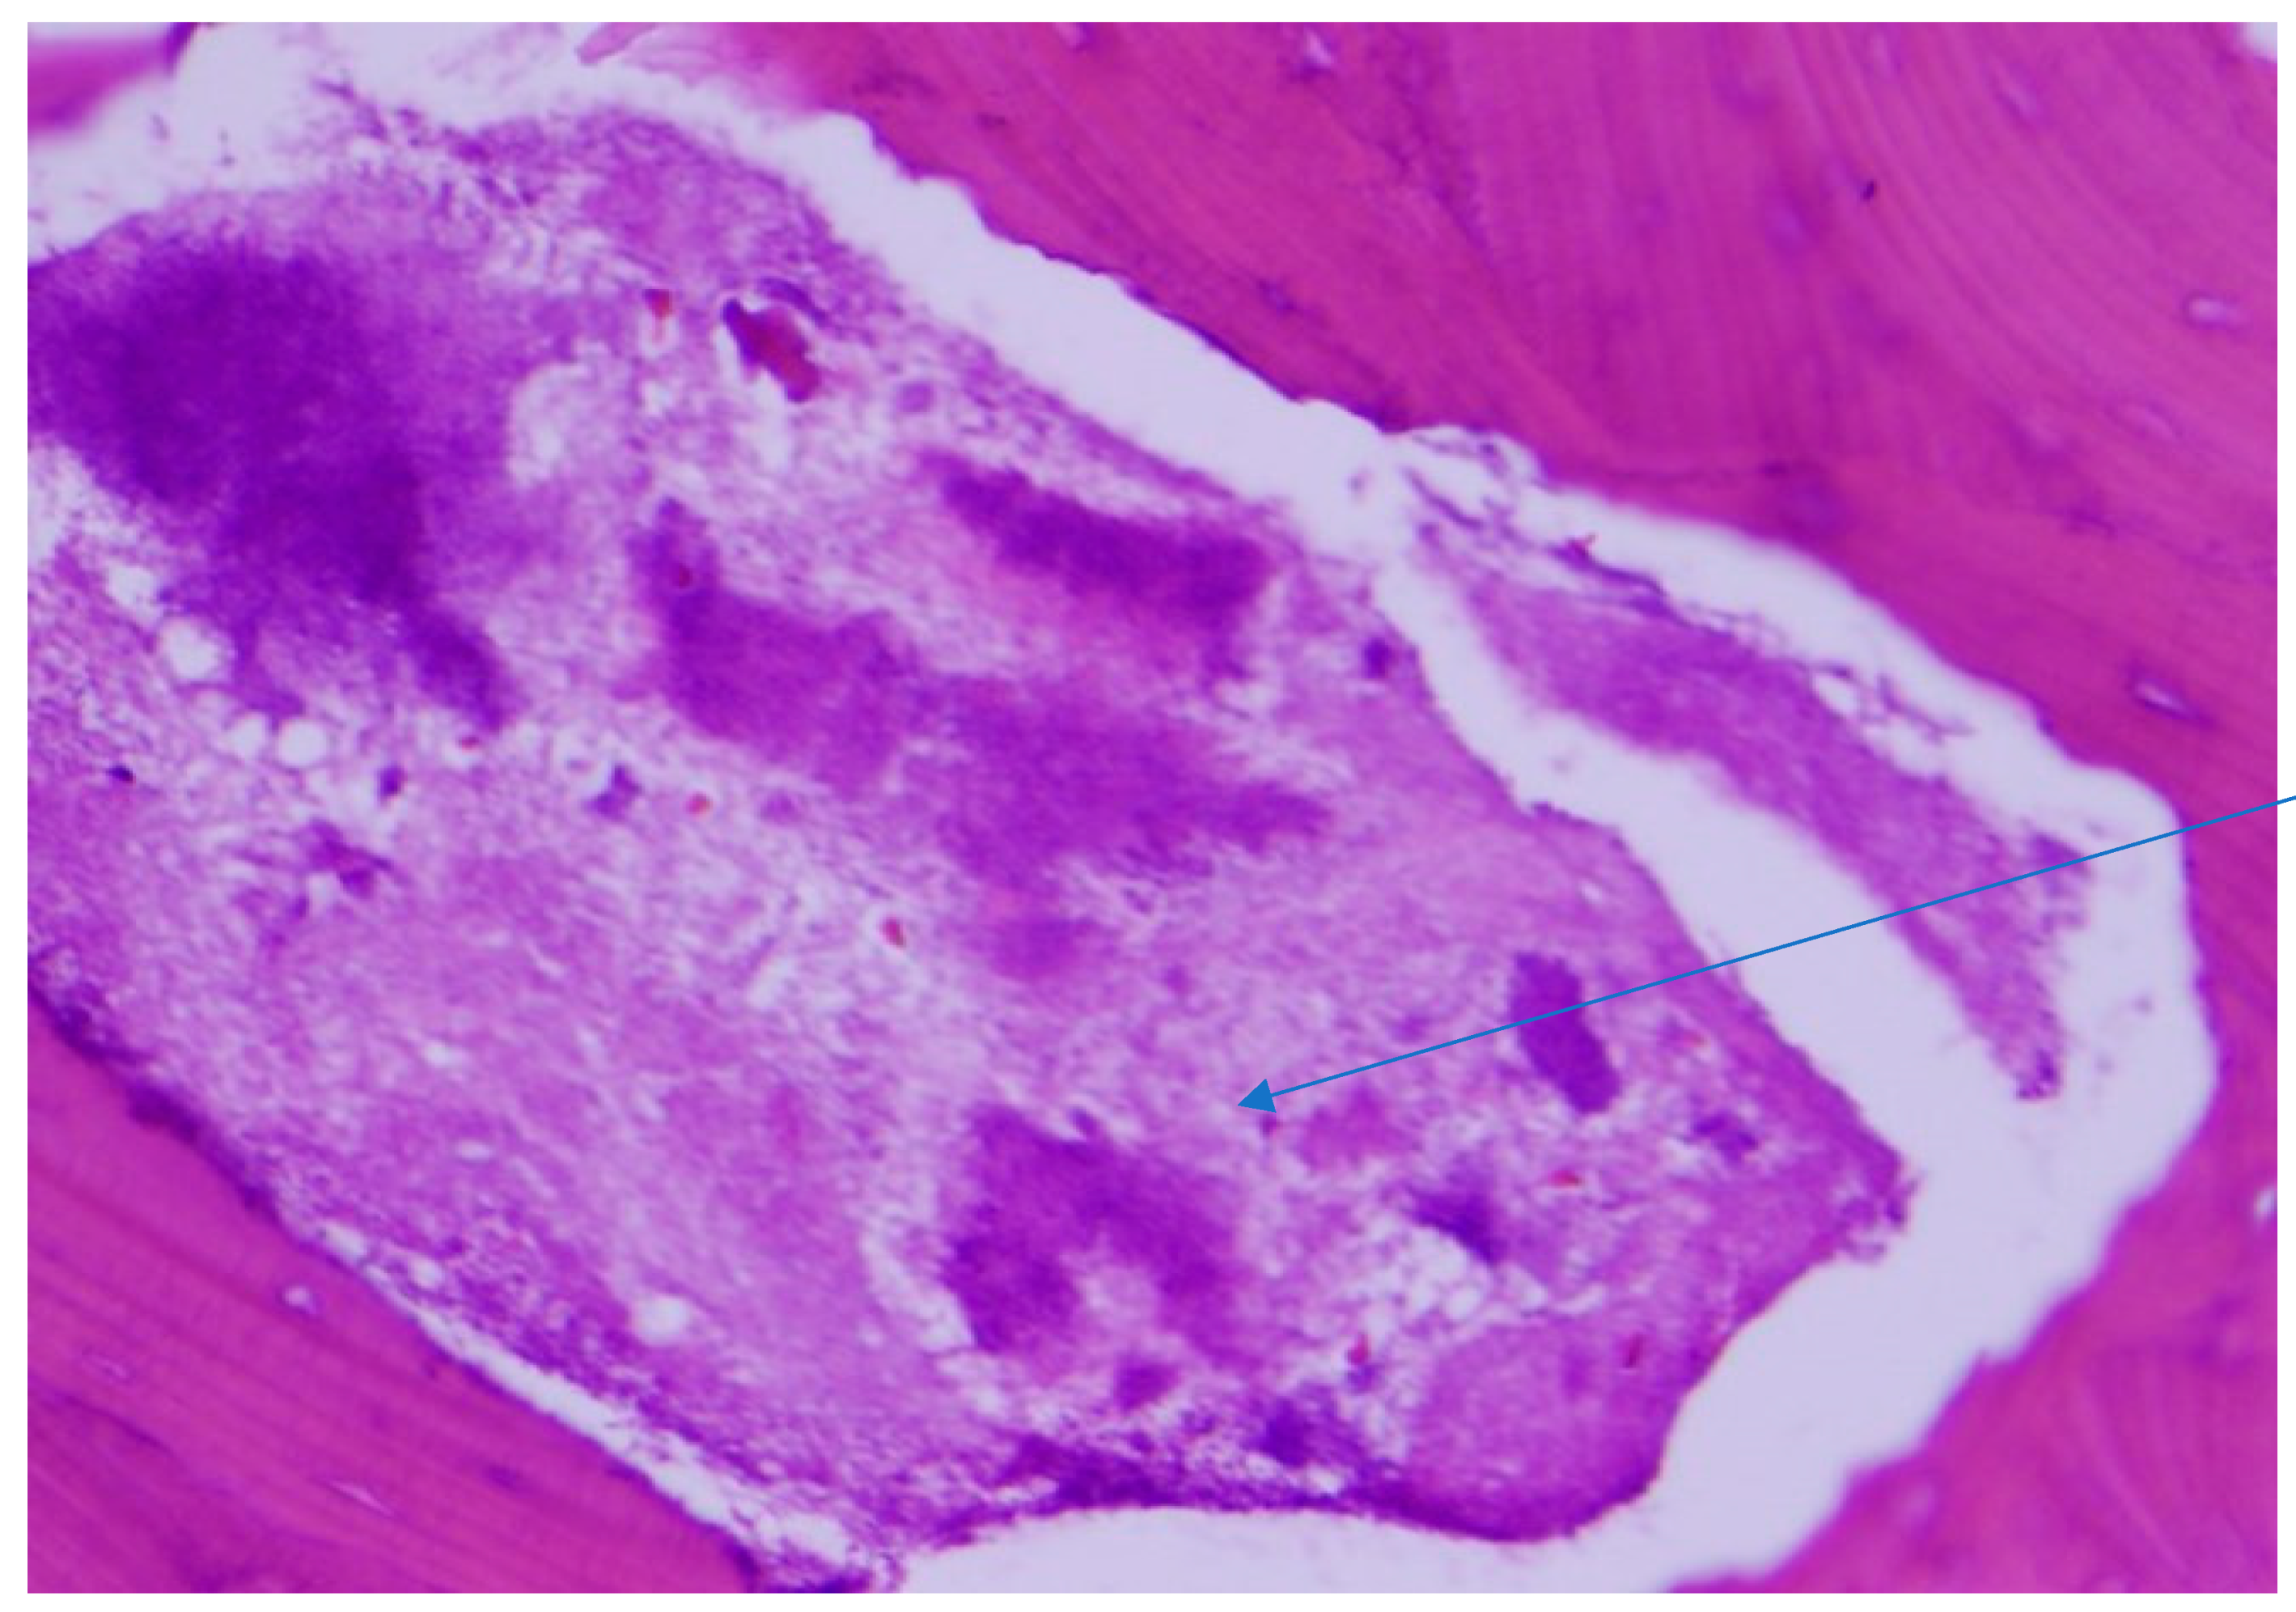

Histopathological examination of the mandibular bone showed osteonecrosis, sulfur granules and embedded organisms on hematoxylin and eosin (H&E) stain (Figure 3 and Figure 4), which were better characterized on Gomori-Grocott methenamine silver stain (GMS) as multiple branching organisms (Figure 5). The official histopathology report read, “acute and chronic osteomyelitis with Actinomyces-like organisms”. A diagnosis of actinomycosis was made, following which the patient was desensitized and treated with intravenous penicillin G for two weeks, followed by oral penicillin VK for six months. He made a complete recovery at the end of therapy with total resolution of symptoms and closure of the exposed bone.

Figure 4.

Sulfur granule (arrow) showing embedded organisms on H&E stain. Original magnification ×200.